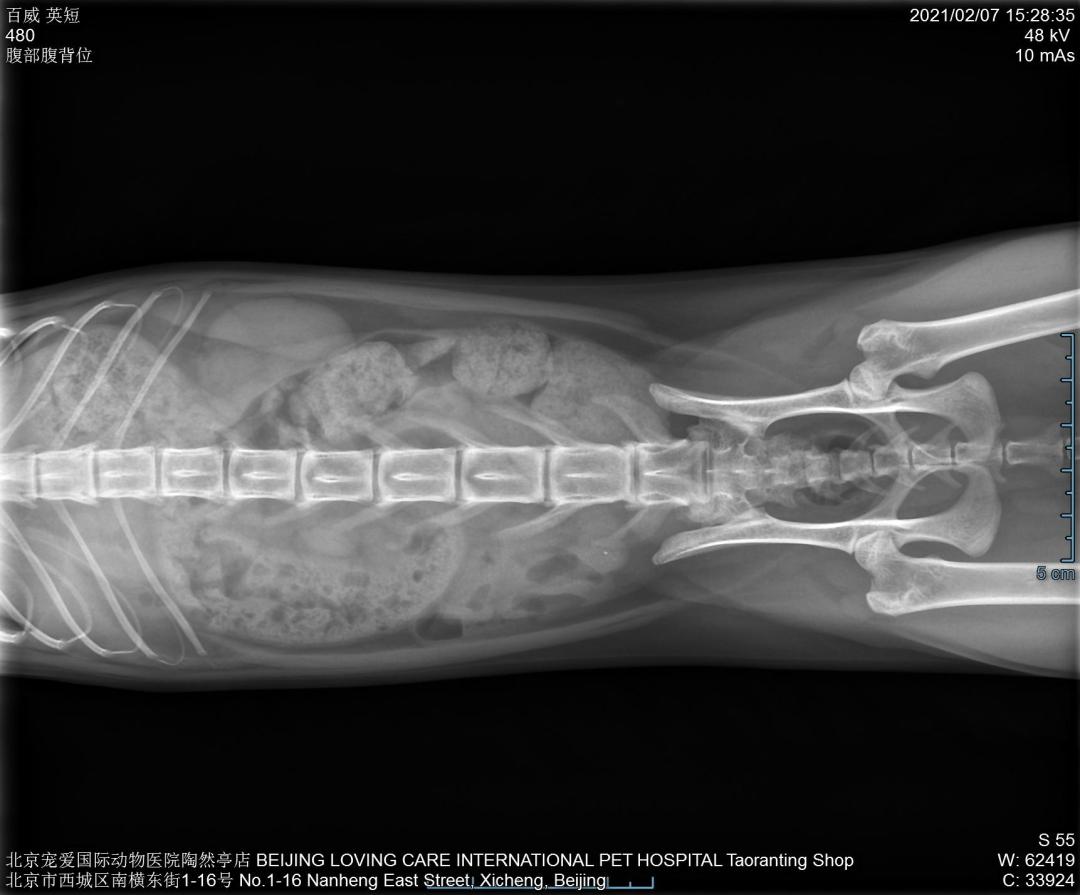

DR检查↓↓

Dr显示膀胱区域高密度影像,膀胱结石。

猫咪尿血来医院检查发现膀胱结石,当天安排了手术,手术前后影像对比,手术将结石全部取出↓↓